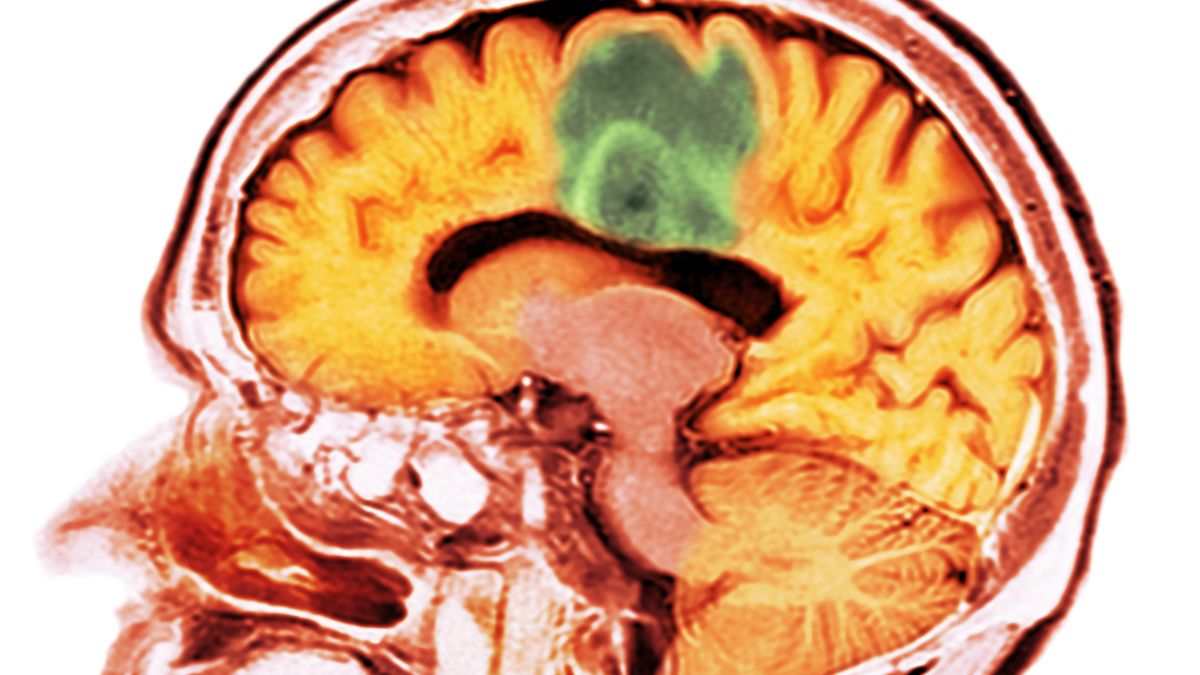

Każdego roku u ponad 2700 osób w Polsce wykrywane są guzy mózgu. Taka diagnoza jest często jak wyrok – według Krajowego Rejestru Nowotworów przeżywa mniej niż połowa pacjentów. Teraz okazuje się, że jest dla nich nadzieja. Naukowcy opracowują szczepionkę, która ma zapobiegać takim schorzeniom.

Naukowcy testują szczepionkę, która ma pomagać zwalczać guzy mózguNaukowcy testują szczepionkę, która ma pomagać zwalczać guzy mózgu

Już wkrótce szczepionka na guza mózgu może być w zasięgu ręki. Niemieccy naukowcy z Heidelbergu i Mannheim pracują nad preparatem, który ma zwalczać zmiany nowotworowe powodowane przez glejaki. Szczepionka ma aktywować naturalną odpowiedź układu immunologicznego na złośliwe białka.

W przeprowadzonym badaniu wzięły udział 33 osoby z różnych grup wiekowych. Choć glejaki mogą występować także u młodszych osób, zazwyczaj dotyczą tych po 40. roku życia. To najczęstszy rodzaj guzów mózgu występujący u dorosłych.

Glejaki są zazwyczaj wykrywane bardzo późno. Trudno jest je w pełni usunąć operacyjnie. Nawet przy jednoczesnym stosowaniu chemioterapii i radioterapii, leczenie jest skuteczne tylko w ograniczonym zakresie.

W 70 proc. przypadków tzw. glejaków rozlanych, czyli rozprzestrzenionych po całym mózgu, występuje jedna konkretna mutacja genu. Modyfikowana jest struktura białka budulcowego w enzymie IDH1. Zdaniem naukowców, układ odpornościowy może w odpowiednich warunkach rozpoznać nowe białko jako obce.